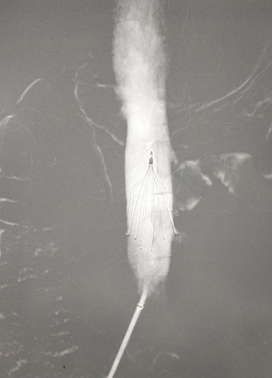

Surgical treatment of pernicious placenta previa with IUD pregnancy under uterine artery embolization

Pregnancy complicated with pelvic vein thrombosis, the operation was completed after inferior vena cava filter placement.